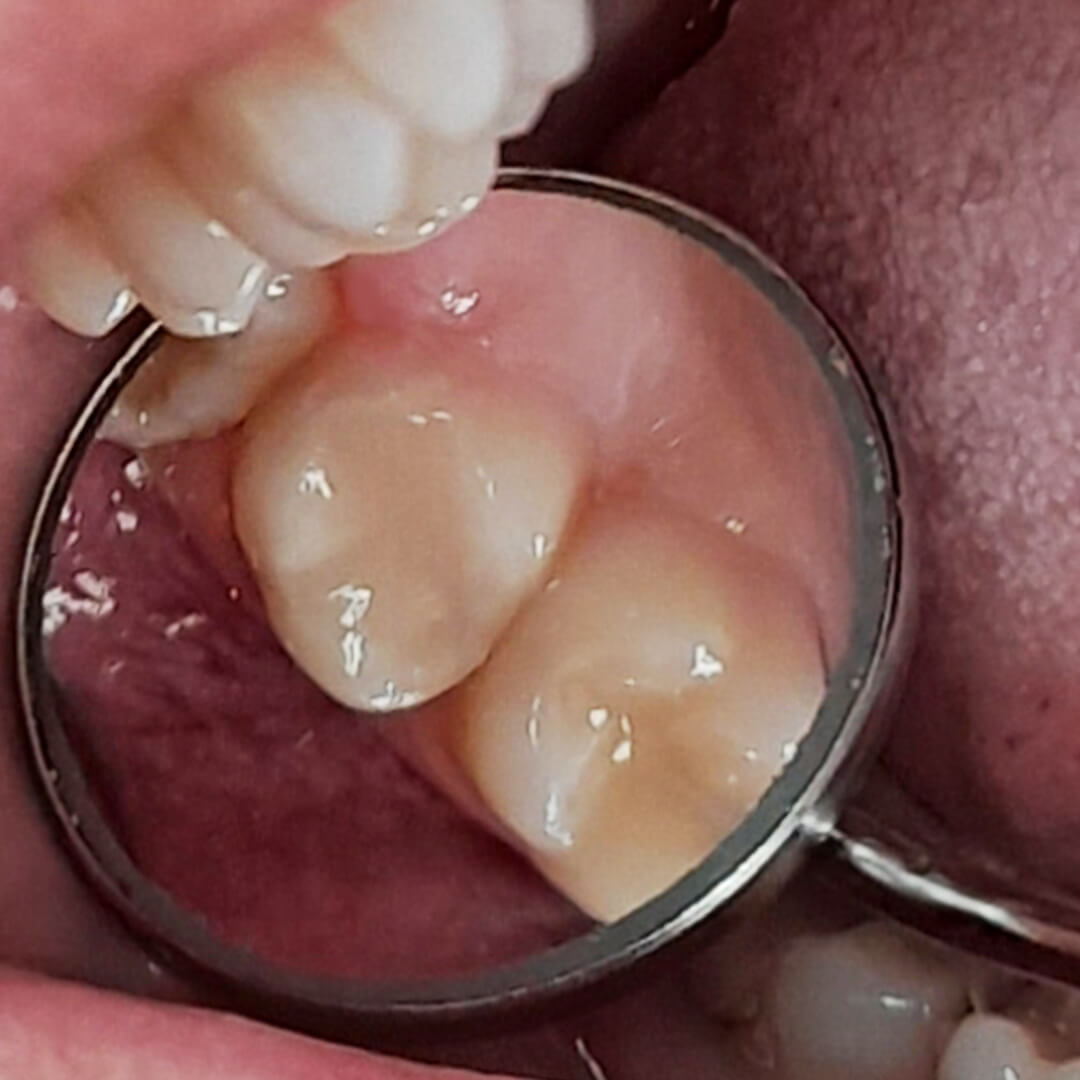

Пациентка обратилась в «Стоматологию Комфорта» с жалобами на кратковременную боль от холодного в области 17 зуба. Врач-стоматолог-терапевт Похилько Надежда Геннадьевна в ходе осмотра выявила кариозную полость на окклюзионной поверхности 17 зуба. Зондирование было болезненно, перкуссия — безболезненна. После препарирования под контролем кариес-маркера был поставлен диагноз: глубокий кариес окклюзионной поверхности 17 зуба. Врач пришёл к выводу о лечении с последующей установкой пломбы из светоотверждаемого композита Estelite.

- постановка пломбы из светоотверждаемого композита Estelite;

Композитный материал Estelite быстро полимеризуется под воздействием светового излучения. Благодаря высоким эстетическим показателям пломбы из этого материала сливаются с естественным цветом зубов. Прочный материал с отличными физическими и механическими характеристиками на 82% состоит из композитного и кремниево-циркониевого наполнителя. Препарат Estelite снижает чувствительность эмали и укрепляет её. Это качество выгодно отличает композит от традиционных материалов для пломбирования.